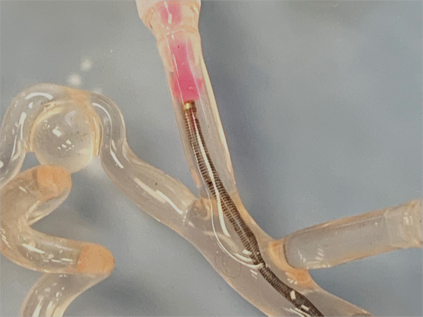

Objective: The objective of this work is to introduce and demonstrate the effectiveness of a novel sensing modality for contact detection between an off-the-shelf aspiration catheter and a thrombus. Methods: A custom robotic actuator with a pressure sensor was used to generate an oscillatory vacuum excitation and sense the pressure inside the extracorporeal portion of the catheter. Vacuum pressure profiles and robotic motion data were used to train a support vector machine (SVM) classification model to detect contact between the aspiration catheter tip and a mock thrombus. Validation consisted of benchtop accuracy verification, as well as user study comparison to the current standard of angiographic presentation. Results: Benchtop accuracy of the sensing modality was shown to be 99.67%. The user study demonstrated statistically significant improvement in identifying catheter-thrombus contact compared to the current standard. The odds ratio of successful detection of clot contact was 2.86 (p=0.03) when using the proposed sensory method compared to without it. Conclusion: The results of this work indicate that the proposed sensing modality can offer intraoperative feedback to interventionalists that can improve their ability to detect contact between the distal tip of a catheter and a thrombus. Significance: By offering a relatively low-cost technology that affords off-the-shelf aspiration catheters as clot-detecting sensors, interventionalists can improve the first-pass effect of the mechanical thrombectomy procedure while reducing procedural times and mental burden.